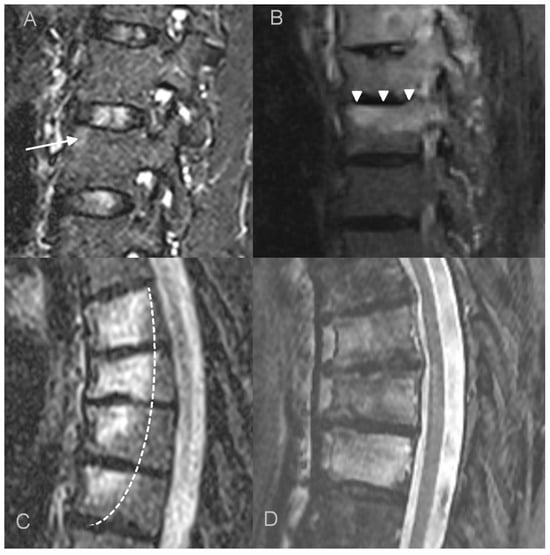

- bone marrow edema (BME) presence and pattern (Figure 1):

Figure 1. Bone marrow edema (BME) patterns appreciated on T2 FS/STIR MRI images. (A). corner inflammatory lesions (arrow); (B). propagating (arrowheads); (C). semicircular/curvilinear (dotted line); (D). diffuse—patchy (in the upper two vertebrae) and solid (in the lowest vertebra).- vertebral body corner inflammatory lesions (CIL)—active Romanus lesion defined as small foci of BME at the vertebral corners,

- propagating BME (larger lesions extending along the endplates),

- semicircular/curvilinear pattern of BME involving the anterior vertebral bodies as described by Peffers et al. and MCGauvran et al. [21,22],

- diffuse solid or patchy BME involving the most of/whole vertebral body,

Bone marrow edema (BME) was present in all 12 patients who underwent MRI. Different patterns of BME coexisted: in most patients, diffuse vertebral body BME was seen (67%), followed by BME propagating along the endplates (50%) and CIL (40%). Semicircular pattern of BME was observed in three patients (25%), However, it involved the highest number of vertebrae (Table 3).